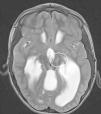

Resultados y conclusionesLa edad promedio de los pacientes fue de 13 años y 2 meses, 7 de los 8 pacientes incluidos tenían discapacidad intelectual, un paciente tenía secuelas neurológicas por síndrome de Dandy Walker y 7 pacientes no tenían alteraciones anatómicas preoperatorias. Después de la cirugía los pacientes mostraron mejoría en la escala Overt Agressive Scale con un promedio de 39,29% (p=0,0156), lo cual se encuentra dentro del rango descrito para TNI en adultos. Los resultados más satisfactorios tuvieron en común la inclusión del complejo nuclear amigdalino dentro de los blancos quirúrgicos. No hubo muertes ni secuelas permanentes atribuibles al procedimiento. La presente serie es la más grande descrita en la literatura hasta el momento para pacientes pediátricos con TNI tratados con ablación estereotáctica.

Results and conclusionsThe average patient age was 13 years 2 months. 7 of the 8 patients enrolled had intellectual disabilities, 1 patient suffered neurologic sequelae referable to Dandy Walker syndrome and 7 patients had no preoperative anatomical alterations. Following surgery, patients with IND noted improvement in their OAS. On average, the OAS improved by 39.29% (P=.0156), a figure similar in comparison to studies assessing treatment of IND in adult patients. The most satisfactory results were achieved in patients whose ablative therapy involved the Amygdala in their targets. There were no deaths or permanent neurological deficits attributable to procedure. To the author's knowledge, this is the largest series described in the literature for pediatric patients with IND treated with lesional stereotactic therapy.